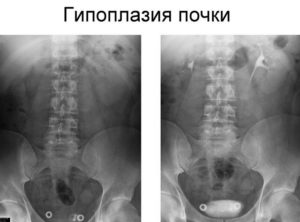

Заподозрить гипоплазию почек можно при проведении ультразвукового исследования, в ходе которого выявляют снижение размеров этого органа. Для уточнения диагноза и проведения дифференциальной диагностики рекомендуется пройти экскретороную урографию, ангиография сосудов почки, ретроградную уретропиелографию.

прочем, в настоящее время вместо этих методов диагностики все чаще применяют магниторезонансную томографию.